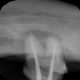

Rentgenowskie zdjęcie będzie także potrzebne czy wręcz niezbędne podczas przygotowań do leczenia kanałowego. Dzięki zdjęciu RTG lekarz będzie w stanie prawidłowo ocenić różne parametry zęba takie jak długość korzenia czy ilość kanałów.